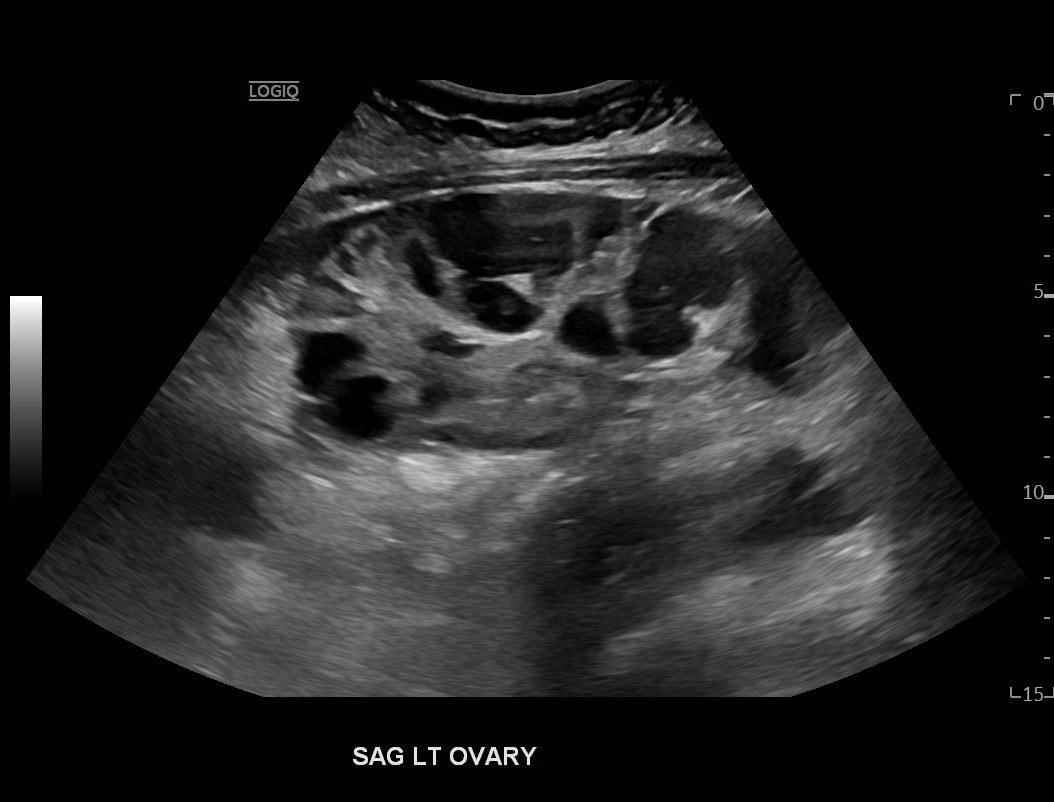

Ovarian hyperstimulation syndrome (OHSS) is a potentially life-threatening complication of assisted reproductive technology (ART). Here, we present the case report of a 30-year-old female undergoing infertility treatment who presented to the emergency department (ED) with nausea and vomiting, abdominal distention, and shortness of breath. On physical exam, she had notable ascites. Computed tomography (CT) of the abdomen and pelvis and pelvic ultrasound (US) revealed significant ascites and enlarged ovaries with multiple cysts. She was diagnosed with severe OHSS and admitted to obstetrics and gynecology (OBGYN) service for five days where she underwent intravenous (IV) hydration and paracentesis. This case report reviews the clinical presentation, categorization, management, and prevention of OHSS and provides examples of imaging findings consistent with the condition.